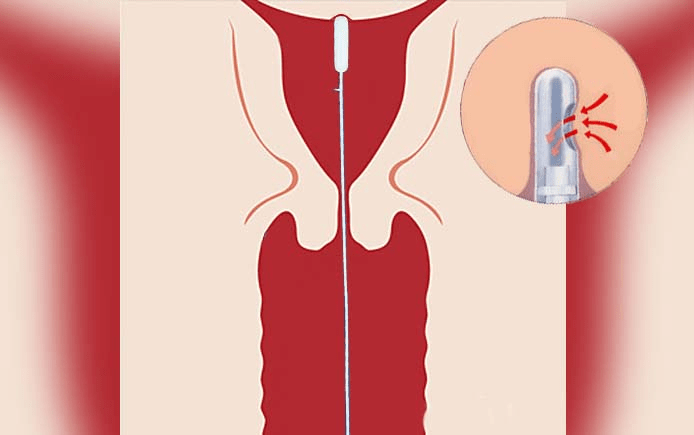

Манипуляция выполняется с помощью специального инструмента – Пайпель де Корнье. По сути, это гибкий одноразовый катетер диаметром не более 4 мм, к которому присоединяется шприц. На боковой поверхности находится отверстие.

Затем нужно определить глубину полости матки и ее направление. С этой целью проводят зондирование, после чего приступают непосредственно к биопсии. В полость вводят пайпель-катетер. Он должен достичь дна матки. Данный процесс отслеживают по шкале, нанесенной на боковую поверхность катетера.

Когда врач убедится, что устройство установлено правильно, он потягивает за поршень. В результате катетер присасывается к стенкам органа, и часть эндометрия попадает в его боковое отверстие. Чтобы получить требуемое количество материала, врач выполняет несколько скоблящих движений. После этого катетер извлекают, а полученный материал помещают в емкость с консервантом или физраствором и направляют для дальнейшего лабораторного исследования.